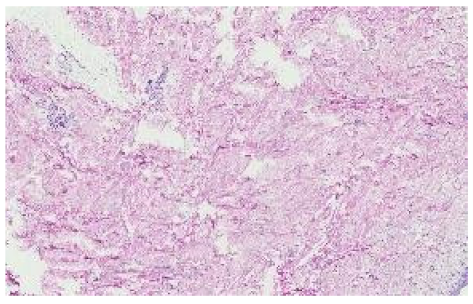

We extracted features identically as in the unsupervised learning set-up above. This approach produced 191 PCs for kidney, 133 for skin, and 151 for colon tiles. Figure 8 showcases skin image tiles after feature extraction along the first two principal components. The remaining tissue types are features in Appendix A and Figure A3 and Figure A4.

Figure 8.

Skin tissue tiles shown along the first two principal components. Colors represent random laboratory tiles. Due to the high number, only a small number of tiles can be shown without occlusion.